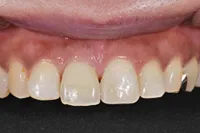

むし歯による前歯欠損の為来院されたケース

■治療前

■歯の根の引き上げ

■治療後

治療のポイント

歯の根の位置を引き上げ、抜歯。その日にインプラント治療へ。

自然の歯と変わらない審美性を取り戻し、非常に満足されています。

| 主訴 | 上顎の真ん中の歯が折れた |

| 治療方法 | 歯の根を引き上げることにより、増骨するので、その後1本のインプラントを埋入し治療した |

| 治療期間 | 約1年 |

| 通院回数等 | 10回 |

| 費用 | 550,000円(税込) |

| リスク・副作用 | 外科治療なしで増骨させた為、治療期間が長くなった |